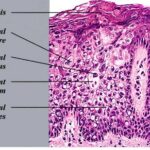

Bowen disease

Bowen disease is a full-thickness anaplasia of the epidermis, with loss of the normal maturation of its components. Keratinocytes are atypical and disorderly, often described as having a windblown appearance. Although the basal cell layer is intact, extension of keratinocyte atypia down the follicular epithelium is seen. Vacuolization, mitoses, individually keratinizing cells, and multinucleated cells are present in the epidermis. Large pale keratinocytes with abundant ground-glass cytoplasm, so-called pagetoid cells, often are distributed haphazardly throughout the epidermis. Hyperkeratosis, parakeratosis, and acanthosis are seen to some degree in lesions of Bowen disease. The upper dermis has a moderate lymphocytic infiltrate.